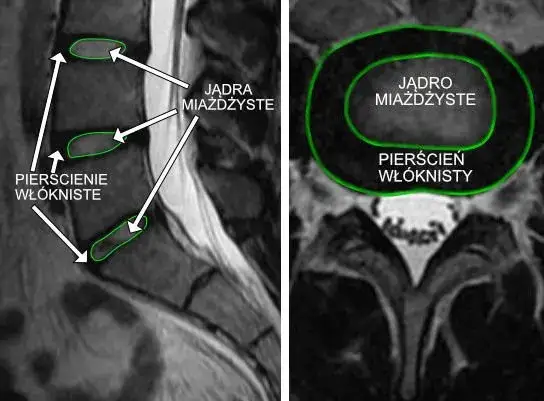

ObjawyZapalenie krążka międzykręgowego objawy: jak je rozpoznać i leczyćKarolina Włodarczyk-13 września 2025